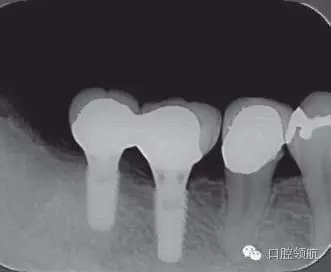

修復(fù)體安裝后的2003年1月復(fù)診時的X線片上,沒有發(fā)現(xiàn)種植體頸部有骨吸收現(xiàn)象,情況良好(圖2)。但是,2003年8月,因混合陶瓷樹脂部分修復(fù)體的破損而進(jìn)行再制作時,發(fā)現(xiàn)有輕度的咬合疼痛以及舌側(cè)頸部的牙齦有輕壓痛??趦?nèi)沒有觀察到該部位的牙齦紅腫。X線片可以觀察到(左下第6顆牙) 的種植體頸部有達(dá)到第4螺紋的骨吸收現(xiàn)象(圖3)。

圖2 沒有發(fā)現(xiàn)種植體頸部的骨吸收(2003年1月)